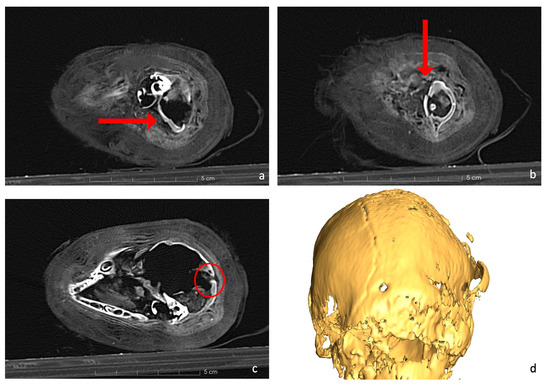

Moreover, the CT scans indicated the presence of materials within the cranium, resembling small bone fragments and the remnants of brain tissue (Figure 8).

Figure 8.

Axial CT scan reveals the evidence of possible brain tissue and tiny bone fragments inside the skull, which are lying on the left side of the mummy (red arrow).

The scans show that the distal epiphyses of the femurs were unfused, as were the proximal epiphyses of the tibiae (Figure 8). Regarding the forelimbs, the proximal epiphyses of the right humerus and the right ulna were unfused, as well as the distal epiphysis of the right radius. All these findings are an indicator of an immature individual [42,43]. The young age is a problem for its taxonomic identification, as the diagnostic skeletal features are not fully developed and biometry is limited to certain skeletal elements. The distal breadth of the humerus (Bd, following von den Driesch, 1979) is 15.8 mm. The humerus was chosen as the distal epiphyses was already fully ossified. Even if a possible slight further growth of the bone cannot be excluded, the size is in line with the variation of Felis silvestris and looks to be too small for the jungle cat Felis chaus [14]. The size overlaps with that of the sand cat Felis margarita [14], but this species is considered to be much rarer and looks to be uncommon in the zooarcheological record in Egypt [16]. If we hypothesize the attribution to Felis silvestris, common amongst votive mummies [47,48], the individual was almost certainly younger than 9 months [43,44]. Furthermore, the dentition was still composed of deciduous teeth, while the permanent molars were unerupted (Figure 3b) and the fourth premolar of the maxilla was still within the chamber (Figure 3a). Since molars erupt at 5 or 6 months, and the eruption of permanent premolars occurs between 4 and 6 months [45], it is possible to hypothesize that the animal was probably less than about 5 months old at death. This age is very common among cat mummies, as other mummies prove [47,48,50].

An intriguing observation in the skull is the presence of various materials within the cranial cavity. There are tiny bone fragments, probably originating from the cribriform plate and the medial wall of the right orbit, which could be a consequence of the desiccation process, which could have compromised their structural integrity and made them highly fragile, causing them to break with minimal handling. Additionally, the possible remnants of brain tissue are observed, located on the left side of the temporal and occipital bone regions (refer to Figure 8). Several studies have reported the appearance of brain residues inside animal skulls due to the dehydration caused by the mummification process [36,52]. Although this could be a possible explanation for the presence of this material, further analysis is needed to clarify the issue.